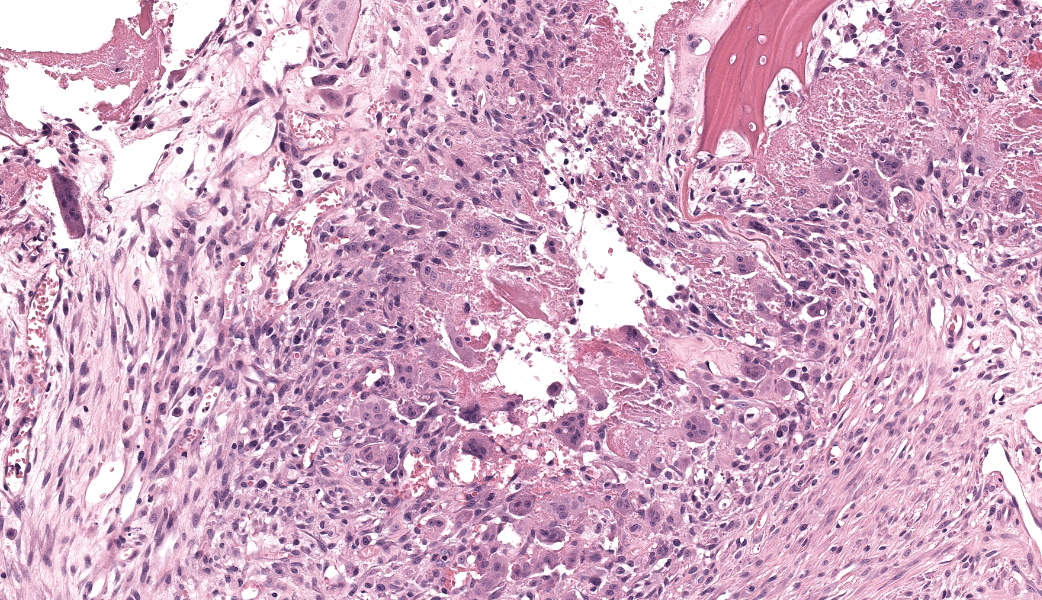

Expanding the anterior uvea, effacing the iris, and markedly expanding the suprachoroidal space is a densely cellular, unencapsulated neoplasm of neuroepithelial cells. Neoplastic cells are arranged in variably dense sheets and as palisading columnar cells surrounding a central lumen (Flexner-Wintersteiner rosettes) or surrounding eosinophilic fibrillar material (Homer-Wright rosettes) surrounded by collagenous and occasionally myxomatous stroma. Neoplastic cells are polygonal to fusiform, have a high nuclear to cytoplasmic ratio, and have distinct cell borders. The nuclei are round to ovoid, finely stippled, and have indistinct nucleoli. There are 16 mitoses in 10 high power fields and anisokaryosis is mild. The neoplastic cells are impinging upon the optic nerve, which has multifocal axonal degeneration and is infiltrated by a population of histiocytes, lymphocytes, and plasma cells, as well as scattered foci of hemorrhage. The retina has multifocal, disorderly components of viable photoreceptor and retinal ganglion cells, dense necrosis, glial scarring, and presumed Mueller cells. The retina is diffusely detached and lacks apparent retinal vessels. The retinal pigment epithelial cells have multifocally migrated through to the inner layers of the retina. The cortical lens fibers are moderately liquefied and homogenous and there is posterior migration of the lens epithelium, consistent with cataractous change. The corneal epithelium has marked, segmental ulceration and the outer corneal stroma in this area is mineralized with occasional breaks and is densely compact with fibrosis. Multifocally throughout the corneal stroma are areas of fibrosis, vascularization, and scattered neutrophils.Contributor's Morphologic Diagnoses:

Medulloepitheliomas are classified as benign or malignant. Criteria for malignancy set forth by Zimmerman et al. include poor differentiation, sarcomatous change, increased mitotic rate or nuclear pleomorphism, and invasion into other structures such as the sclera or uveal stroma.1 In most veterinary cases with continued follow-up, malignancy was rare. In all cases, enucleation is the preferred treatment method.

Intraocular medulloepitheliomas arise from the primitive medullary epithelium of the inner layer of the optic cup. This structure normally develops into the retina, iris, and ciliary body epithelium. This neoplasm most commonly forms in the non-pigmented epithelium of the ciliary body but can rarely originate from the retina or optic nerve. In dogs and cats, intraocular medulloepitheliomas most often follow the playbook and arise from the ciliary body neuroepithelium, but in horses, they tend to go off-book and originate from the optic nerve head.7 Medulloepitheliomas are classified as either benign or malignant, and teratoid or non-teratoid. The teratoid form, as the name would imply, contains tissues that are not present within the normal eye (e.g., cartilage, bone, brain tissue, or muscle). In the conference case, due to the presence of primitive retinal tissue and neuropil within the neoplasm, conference participants favored a ?teratoid? classification for this neoplasm.